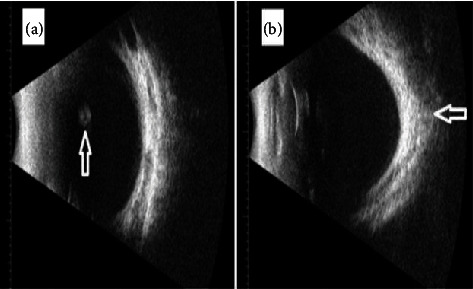

Vitreous cysts represent uncommon ophthalmological conditions. Most patients are asymptomatic, but a minority may experience symptoms such as floaters or blurred vision. Here, we report the case of a 2-year-old girl who was incidentally found to have a vitreous cyst in her left eye during a routine outpatient clinic visit. The cyst was observed to move with eye movements, was pigmented, lobulated, and measured 3 mm in diameter. Our patient exhibited several systemic manifestations. We recommended regular follow-up through clinical examinations and monitoring of the cyst using B-scan ultrasound.

Abstract Image